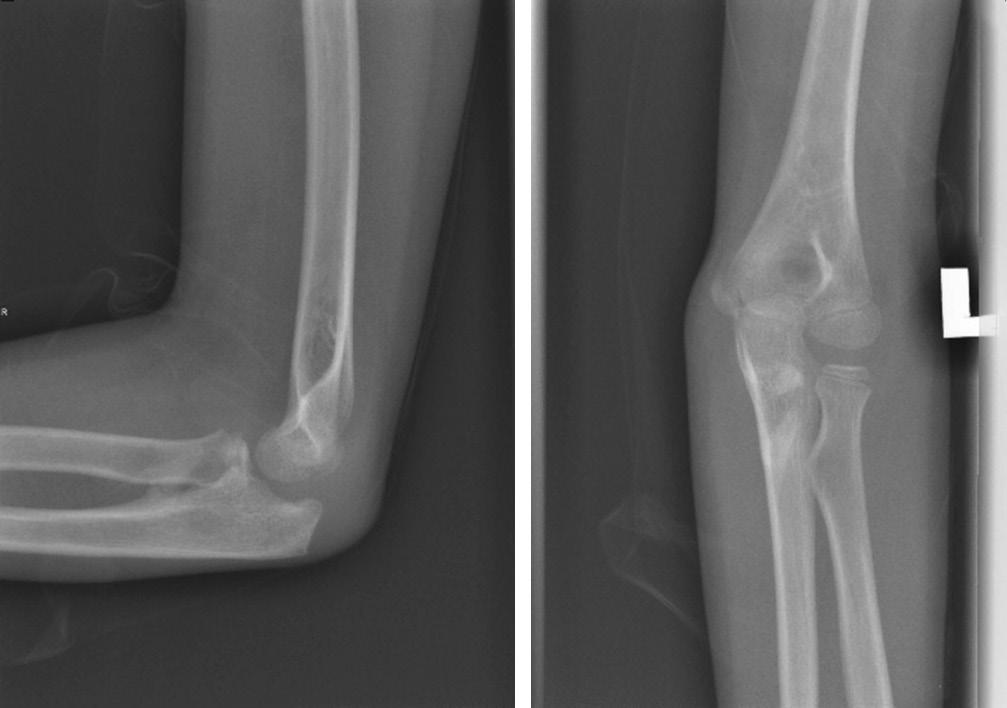

На обзорной рентгенограмме левого локтевого сустава выявлен передний вывих с переломом локтевого отростка (рис. 1). Примерно через два часа после травмы в отделении скорой помощи была предпринята попытка закрытого ручного устранения вывиха, которая оказалась неуспешной. Приблизительно через 6 ч после травмы под общей анестезией выполнено открытое устранение вывиха с чрескожной фиксацией спицей Киршнера. Для ревизии локтевого нерва и репозиции перелома выбран медиальный доступ. Интраоперационно обнаружено ущемление локтевого нерва дистальным фрагментом локтевой кости несколько дистальнее борозды медиального мыщелка. Нерв был натянут, его цвет казался слегка бледным, но целостность была не нарушена. Лучевой нерв был мобилизован проксимально и дистально до исчезновения натяжения. Перелом локтевого отростка произошел в области метафиза, при этом отломок кости был прикреплен в метаэпифизарной зоне, что соответствовало перелому II типа по Salter-Harris. Для репозиции выполнена осторожная контролируемая тракция за локоть. Перелом фиксирован двумя параллельными спицами Киршнера, репозиция головки лучевой кости была спонтанной. Полностью разорванная медиальная коллатеральная связка была восстановлена с помощью рассасывающейся нити 5/0. Интраоперационно оценена стабильность: локтевой сустав был стабилен в супинации, пронации, сгибании и разгибании. После репозиции и восстановления мягких тканей определялась хорошая пульсация на плечевой, лучевой и локтевой артериях. С помощью лонгеты локтевой сустав иммобилизован под углом 90° с предплечьем в положении супинации (рис. 2).

Рис. 1. Обзорная рентгенограмма левого локтевого сустава, на которой виден передний вывих в локтевом суставе с сопутствующим переломом локтевого отростка